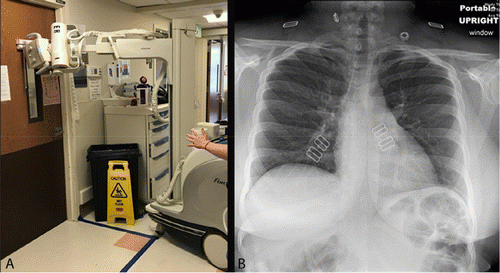

Mobile X Rays Are Highly Valuable For Critically Ill Covid Patients Springerlink

link.springer.com